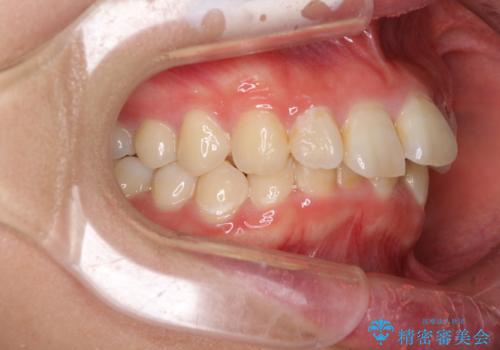

- デコボコの歯列が気になるとことで来院された患者様です。

歯列不正としては軽度であったため、インビザラインでもワイヤー装置でも対応可能でしたが、ご本人の希望によりインビザラインによる矯正治療を行うこととしました。

マウスピース矯正は、自己管理が非常に重要と事前にお伝えしておりましたが、毎日のマウスピース装着が遵守できず、ワイヤー装置での矯正治療へ変更することとなりました。

インビザラインからワイヤー装置へ変更すると、費用が追加となるため、ワイヤー装置は目立つものの費用を抑えることのできるメタルブラケットを使用しました。